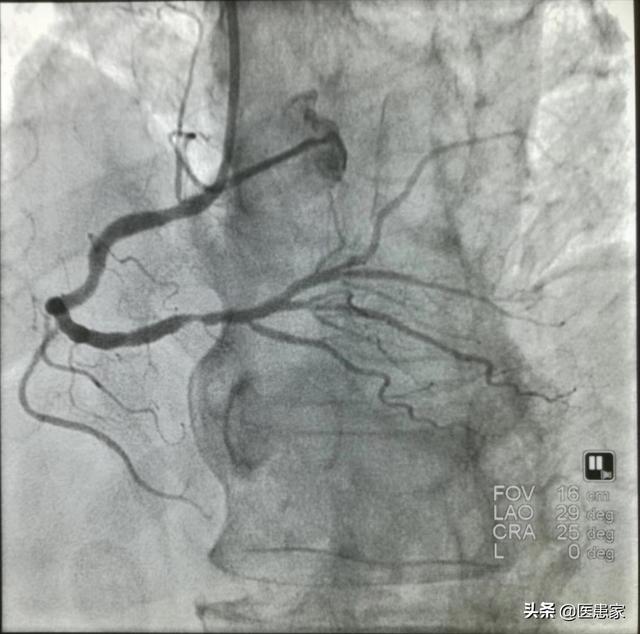

冠動脈造影検査は冠動脈疾患の診断を確定するためのゴールド・スタンダードですが、侵襲的な検査でもあり、患者さんにとっては有害な検査なので、他の検査のようにやりたいときにできるわけではなく、通常は専門医の判断がないと実施できません。

冠動脈造影検査は、患者が起きている間に行われ、(すべてがうまくいけば)10時間以内で終了するが、患者の血管が細く、位置を特定するのが困難な場合は、さらに時間がかかることがあるが、一般的には小手術のような検査と考えられている。

1、医師は患者の右手の動脈を穿刺し、すべての基本となるシースを入れる。

2、造影カテーテルはシースを通して心臓に送られる。

3、造影剤を造影カテーテルから注入し、X線透視で外から見る。

そのため、冠動脈造影は侵襲的な検査であり、あえて必要だと言う医師はいないし、実施するためには多くの条件を考慮する必要がある。